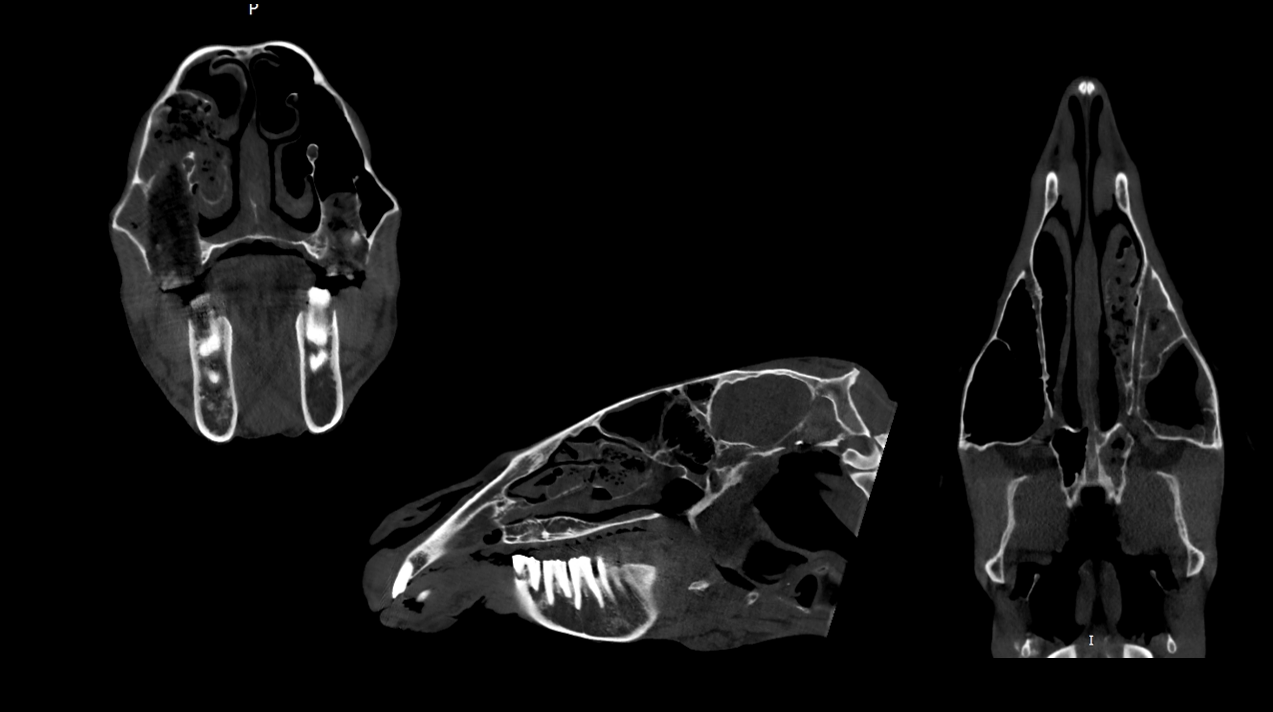

Oronasal Mass

24yo Arabian cross mare

Presented for unilateral left nasal discharge unresponsive to antibiotics.

Additional suspect cancerous lesions found on oral examination and airway endoscopy.